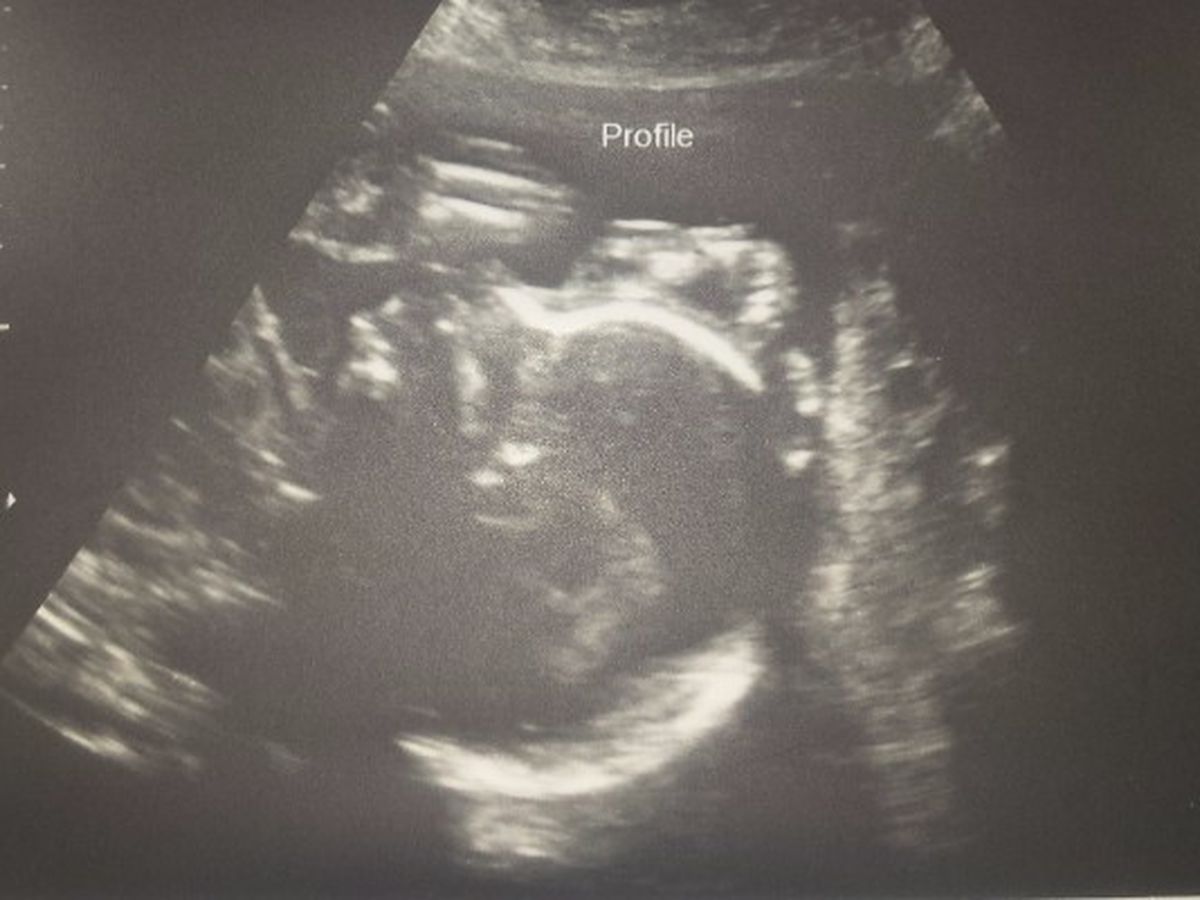

Keri is currently pregnant with her third baby, and first daughter (!) Dahlia. The pregnancy has had some complications, but baby has remained healthy despite. About half way through the pregnancy,at 21 weeks and 3 days, Keri's water broke entirely too early. This event is spontaneous and with no known cause and it is termed previable preterm Premature Rupture Of Membranes. For more information on pPROM I'll add a link or you can simply Google pPROM. This has been devastating for the Putt family. In short, Keri has successfully maintained the pregnancy long enough through two weeks of antibiotics and bedrest to be admitted to the labor and delivery unit of the hospital for steroids and monitoring for the remainder of the pregnancy. This hospital stay could be very short or (hopefully) very long depending on how well Dahlia does and how long she chooses to stay in there. What this means for Dahlia is that she will very likely be a micro-preemie and will have a very long and difficult fight ahead of her! Literally, the fight of her life! We ask that in lieu of gifts, you consider donating, or at the very least, saying some prayers for the family. Keri is currently out of work and lives 1hr from the hospital, so between the daily cost of living, family travel to and from hospital, cost of baby gear, and general expenses that the family will encur over the next few months, the family will be struggling. All donations will be lovingly received and the family will continue to update on progress regularly. Any little bit helps. Thank you all so much!